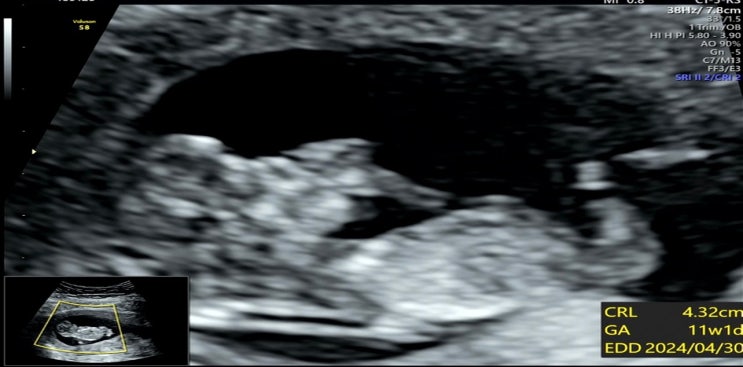

[2023.10.11] 11주 1일. 1차 기형아 검사.

9주차, 10주차를 후루룩 보내고 벌써 11주차가 됐다. 이제 안정기에 가까워져간다. 9주차 때 갈색피는 점차...